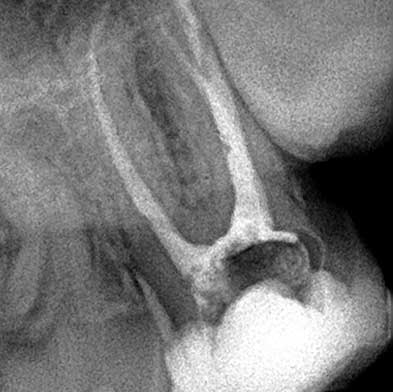

Endodoncia

Dra. Carmen Feito Bárcena